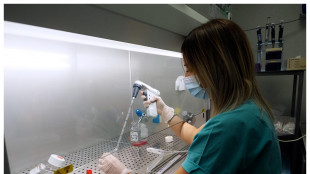

Modelli su misura della Sla per capire gli effetti dei farmaci

Ottenuti in laboratorio da cellule staminali